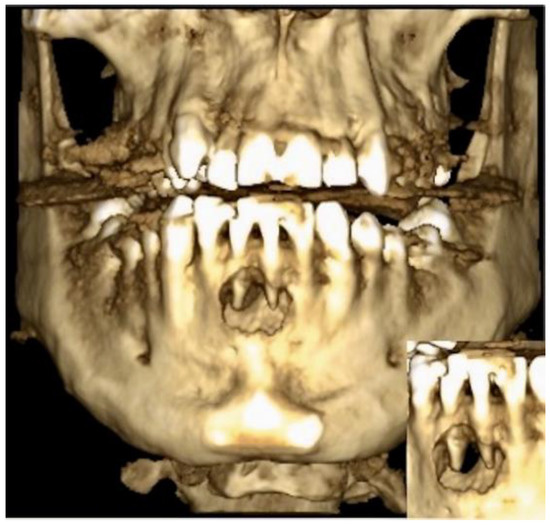

2. Case Description

3. Clinical Procedure and Outcome